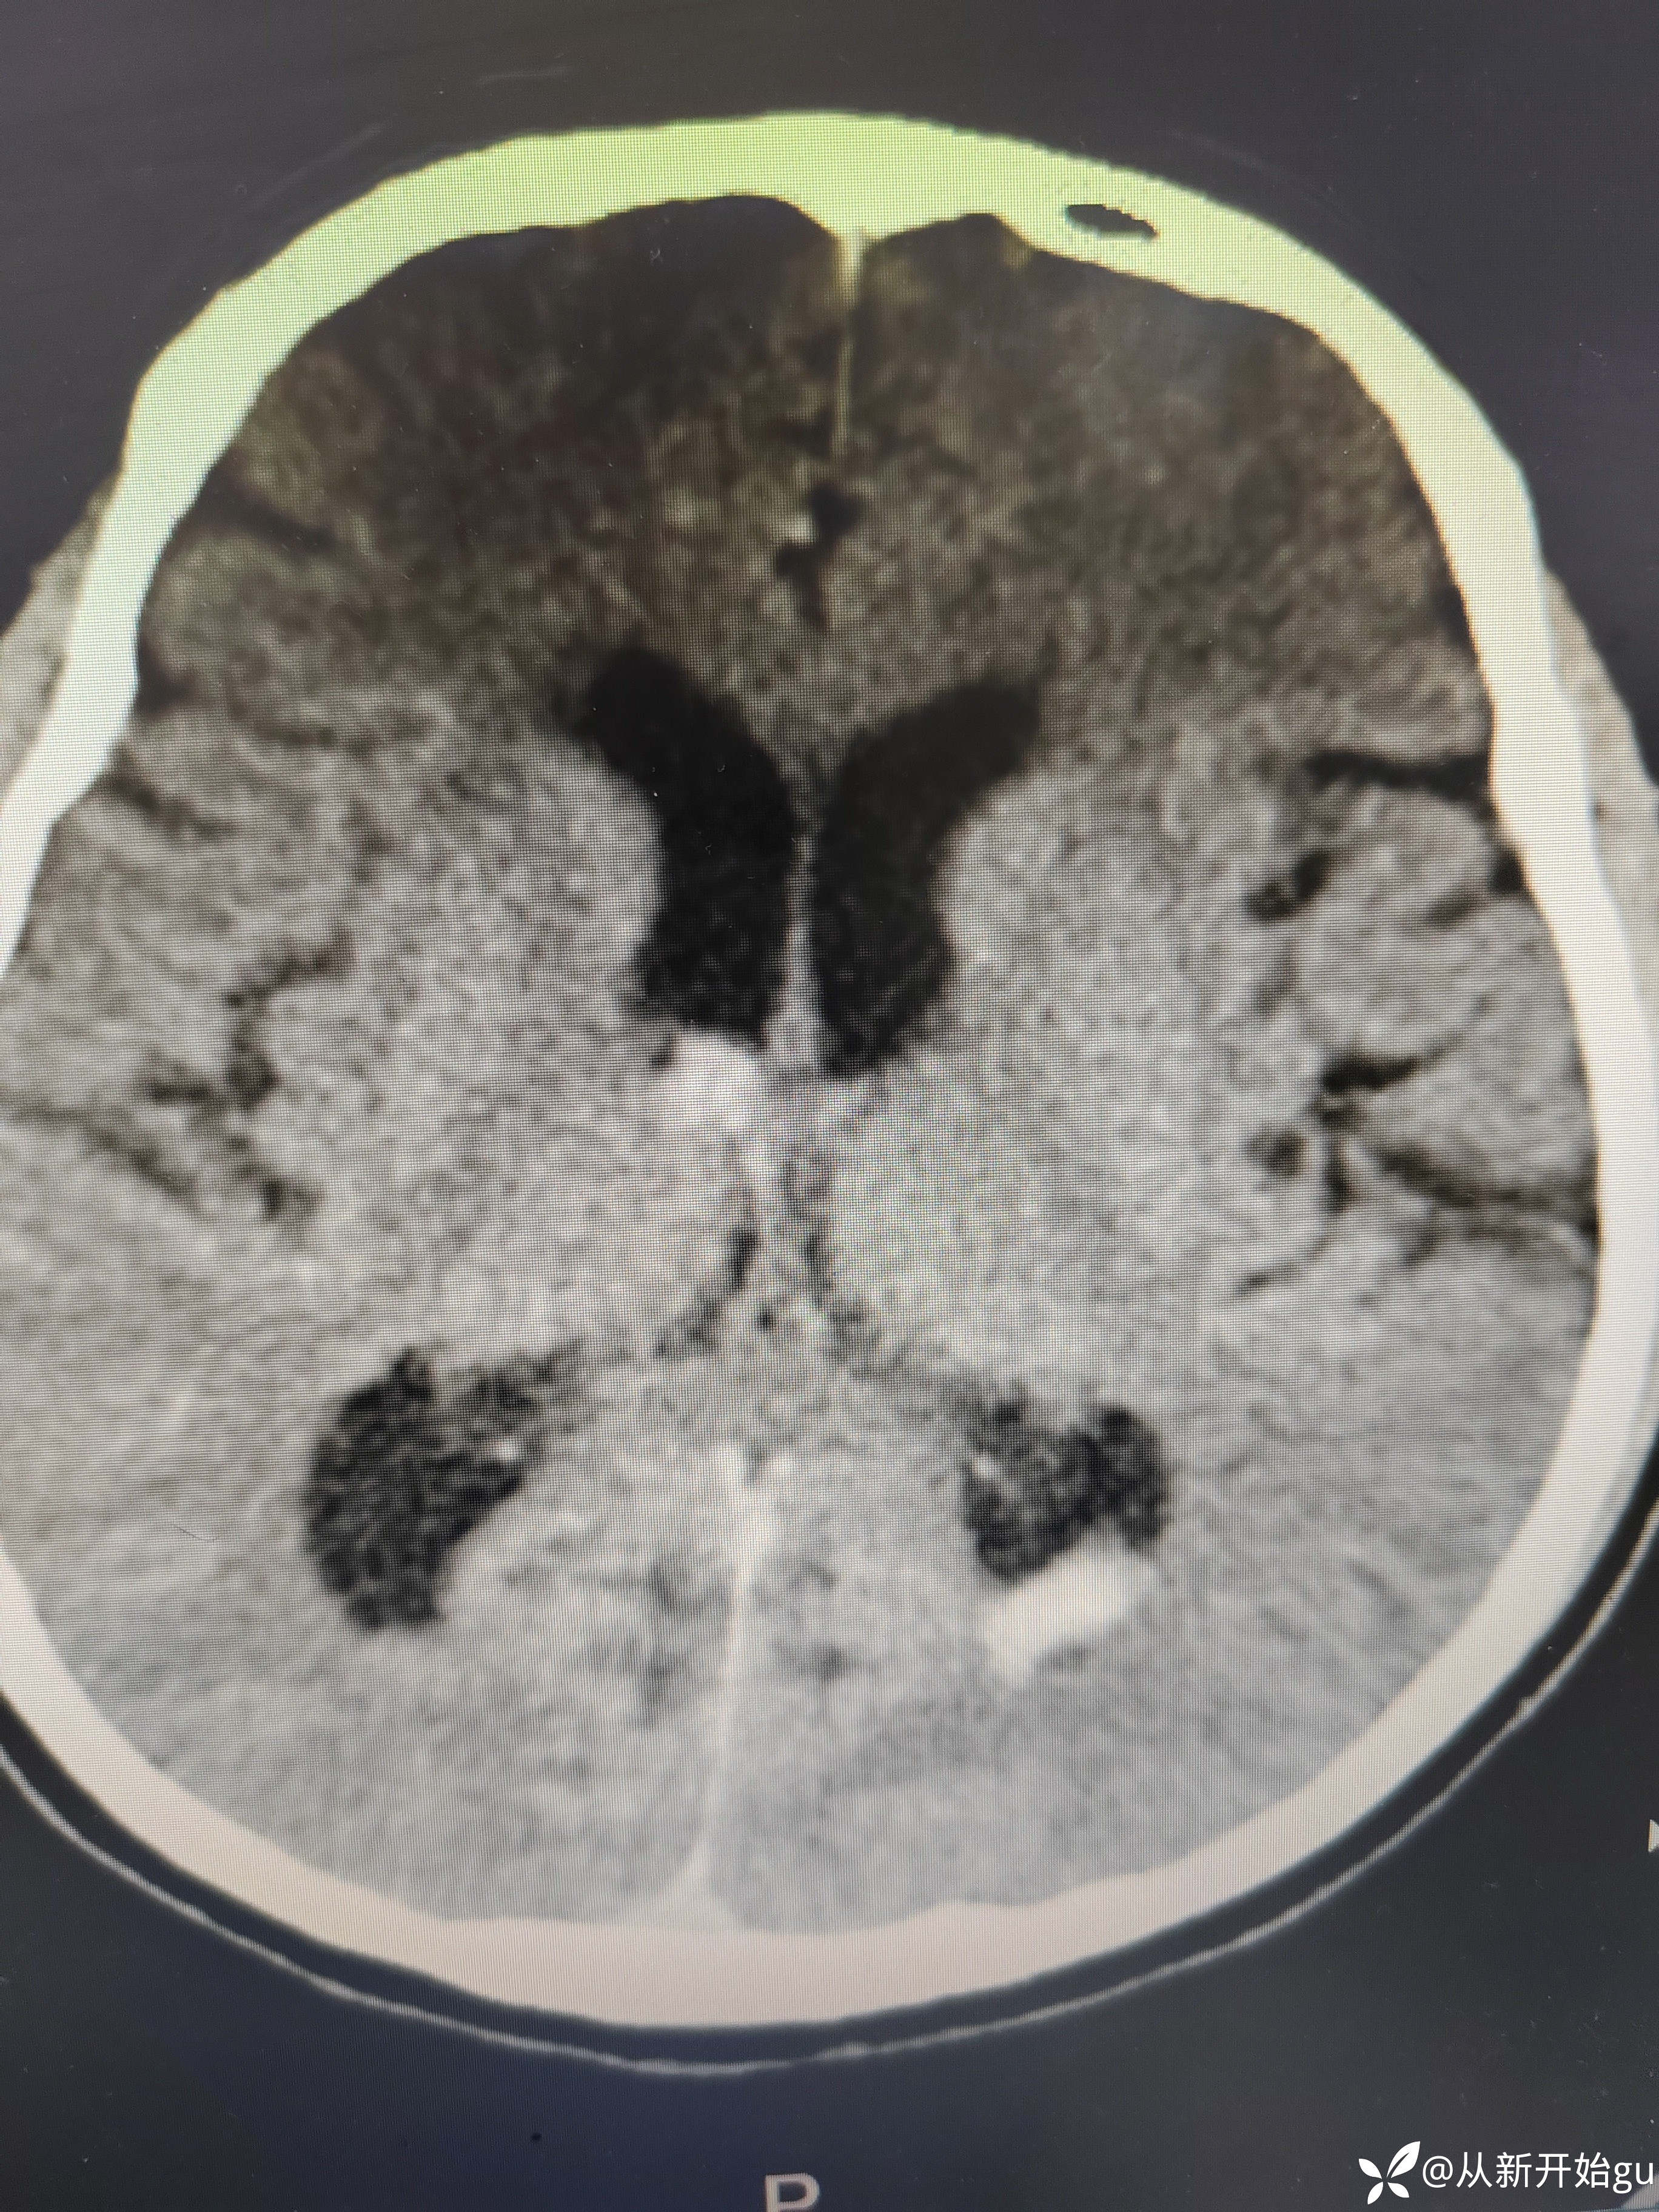

6天后颅脑CT.

6天后颅脑CT.